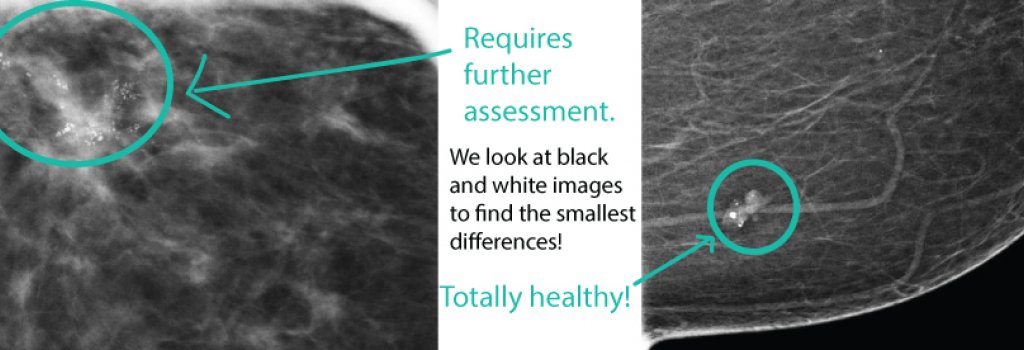

They appear as white spots or flecks on a mammogram but can't be felt during a breast exam. A new group has formed. For women treated for breast cancer in the past, calcifications may also be due.

/meaning-of-breast-calcifications-on-mammogram-430279-01-b5c9cb0c19fa48a39761b7e45a70460b.png)